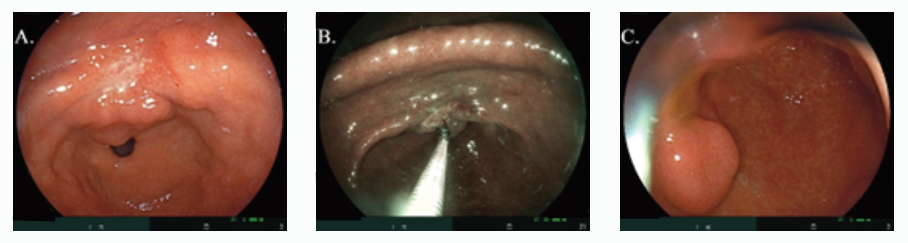

高雄基督教醫院配合國健署辦理「胃幽門螺旋桿菌」糞便抗原篩檢,許多高風險患者也同時接受本院胃鏡檢查,並且檢查出胃潰瘍(圖A和B),或甚至胃部腫瘤(圖C)。建議符合篩檢條件的民眾,盡速接受國健署胃幽門螺旋桿菌糞便抗原篩檢,及胃癌高風險族群定期接受胃鏡檢查,以維護自身健康。

圖A.72歲女性篩檢陽性,自述無明顯腹部不適,但胃竇存有明顯胃潰瘍;

圖B.在特殊鏡頭下,針對胃潰瘍予以切片並送病理檢驗;

圖C.62歲女性篩檢陽性,自述健康,但胃鏡篩檢發現腫瘤。